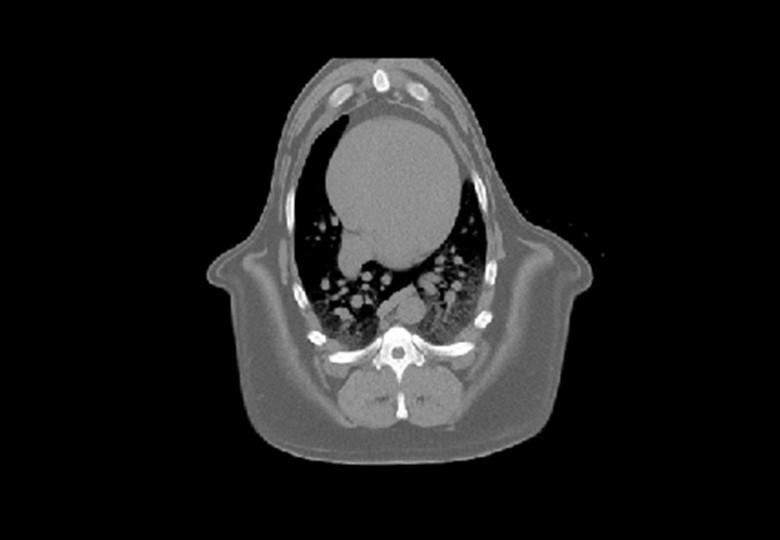

• Poumon